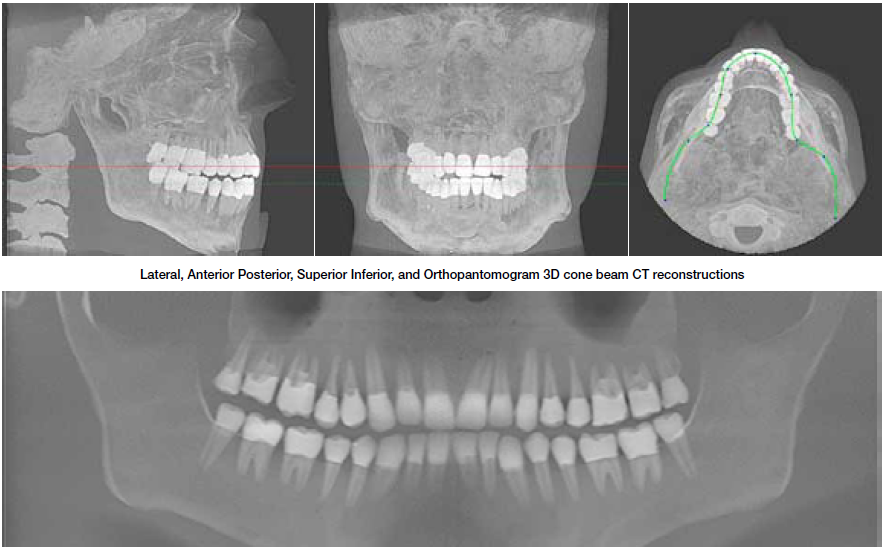

711型牙科診斷用頭模是頭部診斷放射學(xué)的參考標(biāo)準(zhǔn)。模型旨在幫助工程技術(shù)人員和臨床醫(yī)師練習(xí)如何選擇大多數(shù)放射學(xué)程序中常見的掃描參數(shù),并攝片求證是否可以獲得所需的精準(zhǔn)的解剖圖像細(xì)節(jié)。

頭模為研發(fā)人員,臨床醫(yī)師和工程技術(shù)人員在牙科X射線,全景X射線,CT和錐束CT程序培訓(xùn)方面提供了可靠的工具。它是確定系統(tǒng)設(shè)置,調(diào)試新設(shè)備,監(jiān)測(cè)系統(tǒng)性能的理想選擇。

模型包括一個(gè)用于定位在錐形束CT或全景X射線系統(tǒng)內(nèi)的可調(diào)支架。 體模的顎部略微打開,前牙垂直對(duì)齊(接近有一個(gè)咬合導(dǎo)板)的位置,以便牙科掃描系統(tǒng)可以重復(fù)正確定位。 請(qǐng)注意,本產(chǎn)品無法放置實(shí)際的咬合板。

模型由專有的組織等效材料構(gòu)成,模擬人體組織在CT和(50keV-25MeV)治療能量范圍的X射線衰減特性。 體積和結(jié)構(gòu)近似于男性平均頭部。 模型具有詳細(xì)的三維擬人解剖學(xué),包括腦,骨,喉,氣管,竇,鼻腔和牙齒。 骨骼包含皮質(zhì)層和骨小梁部分。 牙齒包括不同的牙質(zhì),牙釉質(zhì)和帶有神經(jīng)的根結(jié)構(gòu)。 竇腔完全打開。

適用于牙科錐束CT和全景X射線的真實(shí)的頜面模型